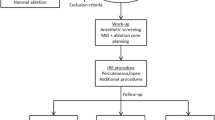

A Axial PET image in a 54-year-old man 5 months after completion of neoadjuvant chemoradiation for distal esophageal cancer shows a focus of increased FDG avidity (arrow; SUVmax 12.8) in the inferior right lobe. B Corresponding axial contrast-enhanced CT image demonstrates a necrotic mass (arrow), consistent with a metastasis.

Common sites of metastatic spread in esophageal cancer include the abdominal lymph nodes, liver, and lungs [10, 23–26]. In one study, it was shown that up to 35 % of patients with esophageal cancer will develop liver metastases [29]. In addition to metastatic disease, the liver is also particularly prone to radiation-induced liver disease during radiotherapy of distal esophageal cancer, due to the close proximity of the left lobe which is accordingly included in the standard radiation field [27–29]. Given that serial PET/CT is increasingly performed during neoadjuvant chemoradiation of esophageal cancer and that both metastases and radiation-induced liver disease may manifest as increased foci of FDG avidity at PET scanning, our study provides important results that address how these two entities might be distinguished. First, we found that new foci of hepatic FDG avidity developing during neoadjuvant chemoradiation of esophageal cancer are usually due to radiation-induced liver disease. Increased FDG avidity in radiation-induced liver disease results from inflammation caused by radiation with increased FDG uptake by active leukocytes [30]. This simple observational result is statistically reassuring, and likely reflects the low likelihood of metastases developing during neoadjuvant chemoradiation. Second, while based on small numbers, we found that the location of the new foci of FDG avidity may be important. All the foci due to radiation-induced liver disease developed in the left and caudate lobes (Fig. 1), within the presumed radiation field, while the sole case of metastatic disease developed in the inferior right hepatic lobe, remote from the primary tumor and radiation field (Fig. 2).